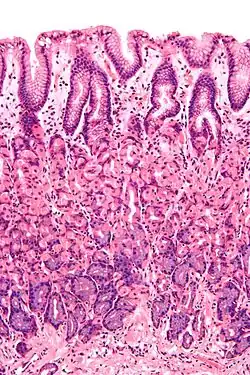

L'épithélium, la partie la plus exposée de la muqueuse, est un épithélium glandulaire avec de nombreuses cellules caliciformes. Les cellules caliciformes sécrètent du mucus lubrifiant qui facilite le passage des aliments et protège la paroi intestinale contre les enzymes digestives. Dans l’intestin grêle, les villosités sont des replis de la muqueuse qui augmentent la surface de l’intestin. Les villosités contiennent un canal chylifère, petit vaisseau connecté au système lymphatique qui aide à emporter lipides alimentaires et fluides tissulaires. Les microvillosités sont présentes sur l'épithélium d'une villosité et augmentent encore la surface par laquelle l'absorption peut avoir lieu. De nombreuses glandes intestinales sous forme d'invaginations en forme de poche sont présentes dans les tissus sous-jacents. Dans le gros intestin, les villosités sont absentes et une surface plane avec des milliers de glandes est observée. La lamina propria, qui contient les myofibroblastes, les vaisseaux sanguins, les nerfs et plusieurs types de cellules immunitaires, se trouve à la base de l'épithélium. La musculeuse muqueuse est une couche de muscles lisses qui favorise l'action du péristaltisme continu et de la catastase dans l'intestin.

- Dans l’estomac, l’épithélium est une monocouche de cellules en colonne et s’organise en fosses et glandes gastriques pour traiter la sécrétion[1]. Dans l’intestin grêle, l’épithélium est une simple monocouche colonne et spécialisé dans l’absorption. L'épithélium est organisé en villosités intestinales, créant une bordure en brosse qui augmentent fortement la surface d'absorption. Chaque cellule a aussi des microvillosités. L'épithélium est donc organisé en plicae circulares et villosités et, de plus, les entérocytes ont des microvillosités à leur surface apicale. Cela crée une bordure en brosse qui augmente considérablement la surface d'absorption. L'épithélium est une monocouche en colonne avec des microvillosités. Dans l'iléon, il y a parfois des plaques de Peyer dans la lamina propria. Les glandes de Brunner se trouvent dans le duodénum mais pas dans d'autres parties de l'intestin grêle[1].